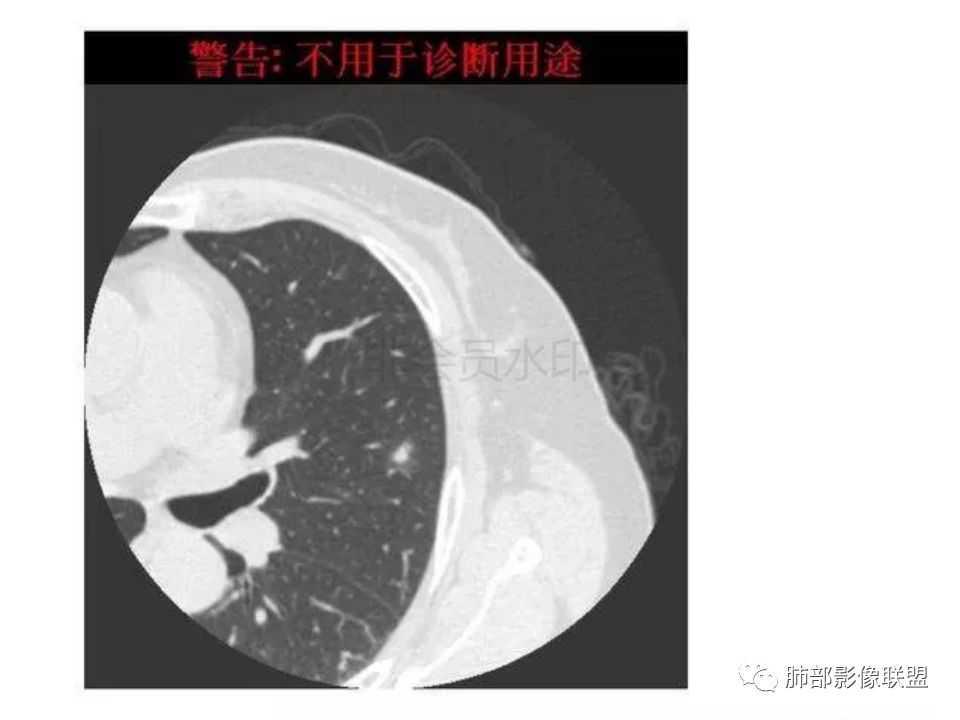

隐球菌感染孤立病灶与肺腺癌结节在影像上有时难分彼此,尽管隐球菌胸膜下更常见。

1.隐球菌病灶往往是实性密度结节为主伴周边边界不清楚的晕,有时可见晕内细软毛刺。

微浸润腺癌常常是磨玻璃密度为主的结节,边界比较清楚,并似乎有弧线形小叶间隔阻挡的痕迹。

实性结节的腺癌则很少有磨玻璃晕,往往会有粗短的硬毛刺。

2.隐球菌病灶形态往往圆钝柔和,缺乏收缩能力,很少出现腺癌的那种胸膜牵拉和棘状突起。

4.隐球菌病灶增强扫描可轻度强化。既不同于结核灶的几乎不强化,也不同于肺腺癌的明显强化。

该患者实性成分为主,可惜未提供增强扫描图像。